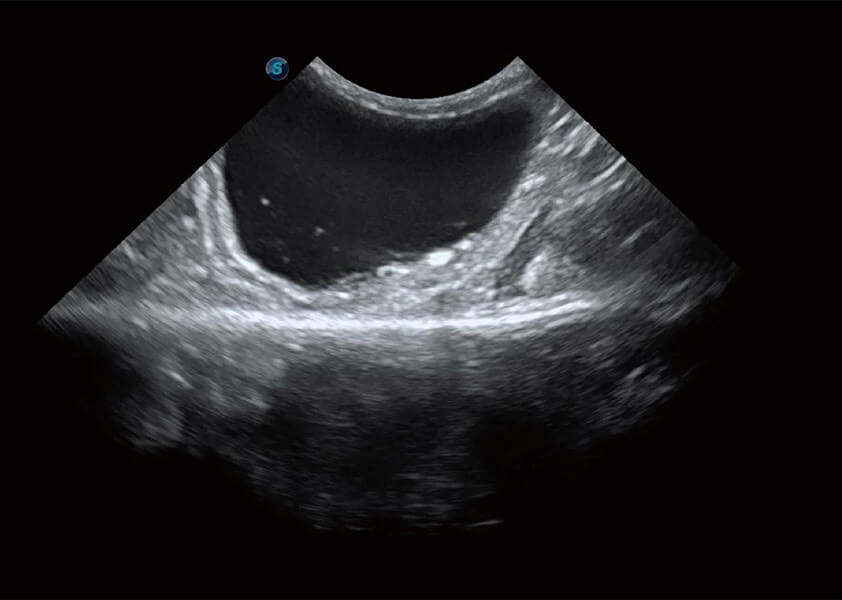

ProPet 60 作為一款高端臺(tái)式動(dòng)物超聲設(shè)備,為動(dòng)物醫(yī)生的日常診斷提供了一系列貼合動(dòng)物臨床需求、解決臨床實(shí)際問(wèn)題的高級(jí)成像功能。憑借全系列高清探頭,滿(mǎn)足醫(yī)生對(duì)腹部、心臟、生殖、淺表、肌骨等成像的所有需求,切實(shí)幫助您提升檢查效率,提高診斷信心。